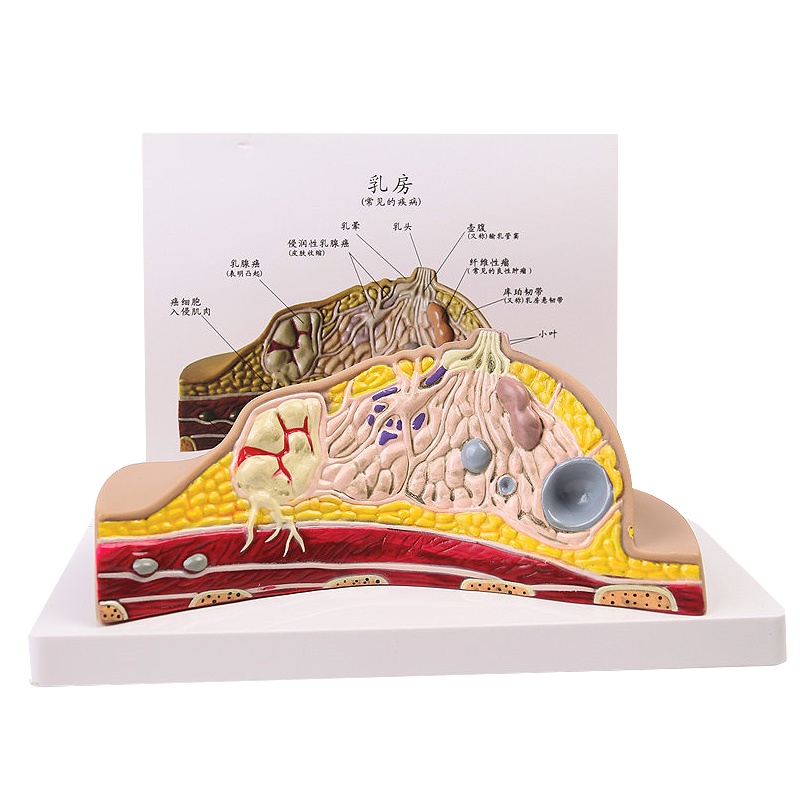

Median Section of Human Female Breast Cancer Anatomical Model Cyclomastopathy Breast Cancer Anatomy Model Medical Study